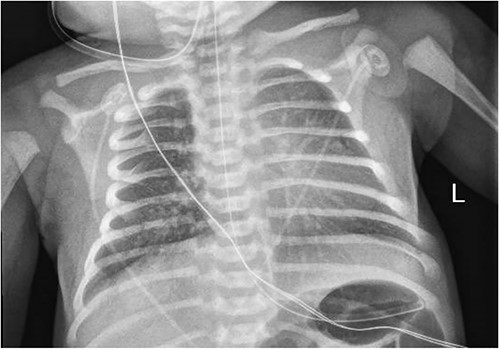

A 3.5 kg male was born via spontaneous vaginal delivery at 38 weeks. A chest radiograph demonstrated opacity at the medial right lung base (Fig. 1) consistent with the known congenital lung malformation. An abdominal ultrasound demonstrated a simple cyst with a gut signature consistent with an enteric duplication cyst (Fig. 2).